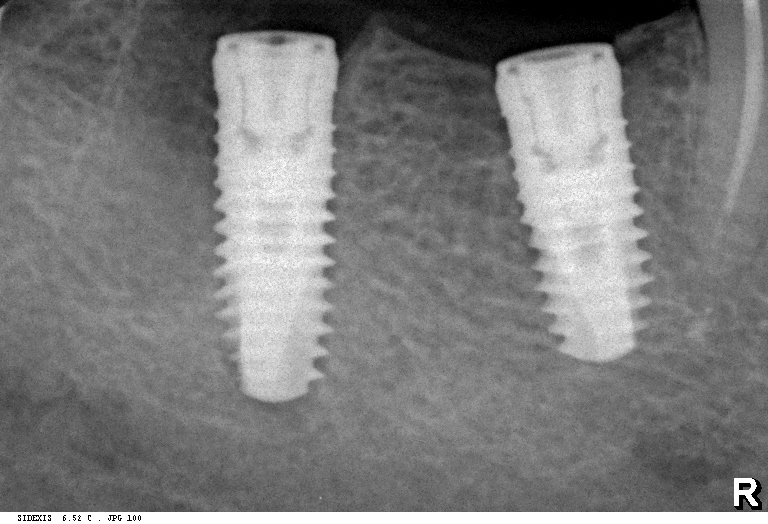

Вот пациент, ему больше пятидесяти лет. Мы удалили восьмерку и семерку, затем поставили два импланта: один в лунку седьмого зуба, а второй — на место давно отсутствующей шестерки. Снимок, сделанный сразу после имплантации (слева). Через 2,5 месяца после имплантации (справа):

На левом снимке хорошо видны края лунки зуба. На правом они, практически, незаметны. Альвеола семерки при имплантации ничем специальным не заполнялась — только кровяной сгусток и немного костной стружки, которая попала туда при подготовке лунки под имплант. И мы видим, что костная ткань великолепно регенерирует — у нее появился характерный рисунок из балок и полостей. Мы видим, что не происходит убыли костной ткани, она не проседает и никуда не уходит. Причина тому — РЕГЕНЕРАТИВНЫЕ СПОСОБНОСТИ организма.